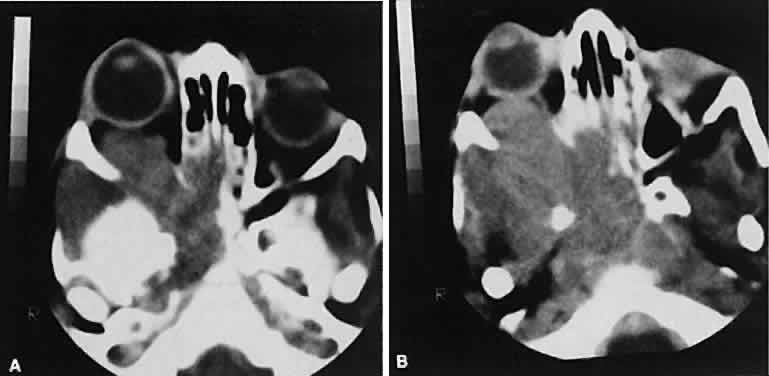

An appreciation for the various pathologic processes that affect the orbit is facilitated by an understanding of the normal orbital anatomy (Fig. 1). The orbit is a pyramid-shaped bony structure bounded inferiorly by the maxillary sinus, medially by the ethmoidal sinus, and superiorly by the frontal sinus. The sphenoidal sinus is situated posteriorly along the medial orbital wall and has a common wall with the optic canal. The lacrimal gland lies within its fossa located in the superior temporal aspect of the orbit and can be seen on both axial and coronal views.

The extraocular muscles (EOMs), with the exception of the inferior oblique, originate from the anulus of Zinn in the orbital apex. The inferior oblique takes its origin from the frontal process of the maxilla and is seen occasionally on CT imaging. The superior oblique, after originating from the anulus, courses along the superior nasal orbital wall just above the medial rectus muscle before passing through the trochlea. The rectus muscles conveniently form a muscle cone, which is sometimes helpful in terms of differential diagnosis. Before thinner axial slices and multiplanar imaging were available, an enlarged inferior rectus muscle often was imaged as an apical mass, especially if dysthy-roid optic neuropathy was present. The importance of imaging from two different planes cannot be overemphasized in this situation.

The superior ophthalmic vein (SOV) is an important vascular structure to recognize. It begins in the superior nasal quadrant near the trochlea before coursing posteriorly and laterally beneath the superior rectus muscle, exiting the orbit through the superior orbital fissure. Drainage is into the cavernous sinus. Asymmetric enlargement, especially in the presence of an ipsilateral cavernous sinus enlargement, suggests a vascular anomaly, which may require selective carotid angiography for further definition. Enlargement of one or multiple EOMs in this setting is likely. The SOV also may be enlarged as a result of any process impeding drainage from the orbital apex, such as dysthyroid orbitopathy or metastatic disease.

The optic nerve occupies the central intraconal space. By necessity, the nerve has a certain amount of slack, which is necessary to permit movement of the globe. In the axial plane, the optic nerve has an undulating course and thus may appear thicker or thinner as a result of partial volume averaging as it passes in and out of the axial plane. It is imperative to recognize this normal pattern for proper interpretation of axial images.

The optic nerve itself is invested by the same meningeal layers that cover the brain, and the intracranial space may extend along the course of the optic nerve to the back of the globe. Enlargement of this space may be recognized as pseudomeningoceles of the optic nerve sheath. It is sometimes possible to tell whether the nerve, the sheath, or both are enlarged by CT scanning, although MRI affords the better view.